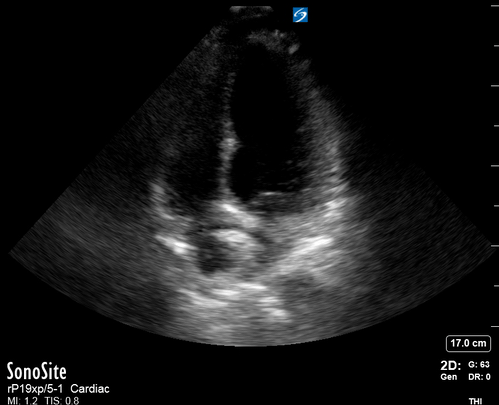

Equality: is the RV dilated or significantly impaired?

Normally, the RV is a low-pressure, thin-walled, high-compliance chamber that wraps anteriorly around the muscular, cone-shaped LV. The normal RV : LV diameter ratio is 0.6 : 1.

When the pulmonary artery pressure rises, the RV will dilate, altering the normal RV:LV ratio. Although sacrificing sensitivity, the use of equality (1:1 ratio) as a cutoff can achieve a specific estimation of RV strain. If imaged correctly by a trained operator, the presence of an RV:LV ratio > 1 is highly specific for RV strain.

RV dilation can be acute, chronic, or acute-on-chronic. However, in patients presenting with undifferentiated chest pain, shortness of breath, hypotension or syncope, the presence of any RV dilation should raise suspicion for acute pulmonary embolism (PE). Furthermore, in a patient in shock, the presence of RV strain may signal the need for aggressive therapy – emergency thrombolysis.

THE VIEWS

The A4C view provides an accurate chamber size comparison. However, achieving a proper A4C view (avoiding foreshortening or ballooning, and visualising the four chambers with a vertically oriented interventricular septum) can be a challenging exercise of image acquisition. Additionally, the PSAX view at the level of the papillary muscles shows both LV and RV side by side and is useful to assess function and size. When RV pressure is high, the septum will be pushed and flattened towards the LV, resulting in the characteristic “D-shaped” LV or “D sign”.

PITFALLS

When comparing size, beware of correct image acquisition, as oblique planes lead to misinterpreting the RV:LV ratio. For apical views be sure to slide the probe sufficiently laterally on the chest wall so that it lies over the true apex. Also, be sure to obtain a real horizontal plane, avoiding foreshortening (ballooning). For the PLAX view it is useful to fan through the heart’s long axis, making sure that LV visualization is maximized relative to the RV. Furthermore, an understanding of probe placement and marker orientation conventions is fundamental. If inadvertently scanning in reverse orientation, the normally larger LV could be mistaken for an abnormally enlarged RV.